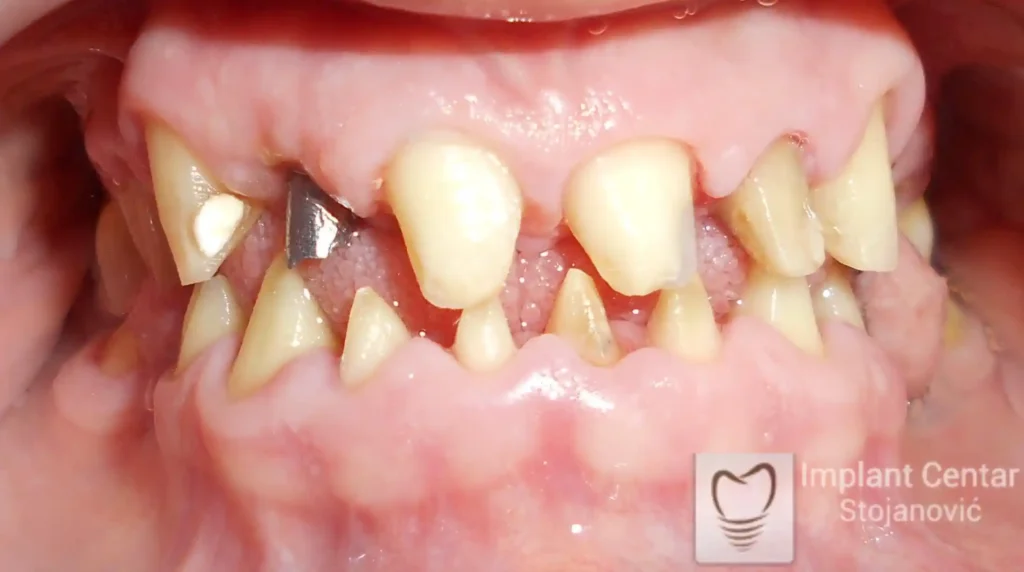

Na slici 1. slici 2. vidi se početno stanje — pacijent je imao prirodne zube, ali samo izradom novih mostova nije bilo moguće postići normalan odnos gornjih i donjih zuba (eugnatan zagrižaj).

Zbog toga je plan terapije uključivao vađenje svih preostalih zuba i ugradnju implantata u gornjoj i donjoj vilici. U gornjoj vilici postavljena su i dva tuberopterigoidna implantata, kao zamena za sinus lift proceduru, što se može videti na ortopan snimku nurađenom odmah nakon ugradnje (slika 3).

Već tri dana nakon operacije, pacijent je zbrinut fiksnim privremenim zubima na implantatima, čime je odmah povraćena funkcija i estetika osmeha.

Nakon završetka perioda integracije implantata, izrađeni su cirkonijum-keramički mostovi u gornjoj i donjoj vilici (slika 6.).

Pacijent ističe da je prezadovoljan rezultatom — po prvi put nakon dugo vremena može normalno da žvaće i grize hranu, uz prirodan izgled novog osmeha.